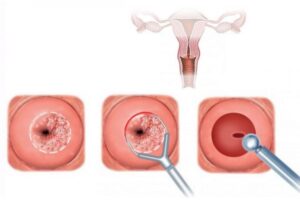

Τα βλαστοκύτταρα είναι ειδικά κύτταρα που βρίσκονται στον λαιμό της μήτρας (τράχηλος) και παρακολουθούν τις αλλαγές στις κυτταρικές δομές που μπορεί να υποδεικνύουν την παρουσία προβλημάτων, όπως προκαρκινώματα ή καρκίνος του τραχήλου της μήτρας. Αυτή η διαδικασία γνωστή ως εξέταση Παπ (Pap test) είναι ένα σημαντικό εργαλείο στην πρόληψη και τον έγκαιρο εντοπισμό καρκίνου του τραχήλου της μήτρας.

Τα βλαστοκύτταρα είναι ειδικά κύτταρα που βρίσκονται στον λαιμό της μήτρας (τράχηλος) και παρακολουθούν τις αλλαγές στις κυτταρικές δομές που μπορεί να υποδεικνύουν την παρουσία προβλημάτων, όπως προκαρκινώματα ή καρκίνος του τραχήλου της μήτρας. Αυτή η διαδικασία γνωστή ως εξέταση Παπ (Pap test) είναι ένα σημαντικό εργαλείο στην πρόληψη και τον έγκαιρο εντοπισμό καρκίνου του τραχήλου της μήτρας.

Ο γυναικολόγος εκτελεί το Παπ τεστ κατά τη διάρκεια γυναικολογικής εξέτασης, καθώς και άλλων εξετάσεων, για την παρακολούθηση της υγείας του τραχήλου της μήτρας και του γυναικολογικού συστήματος γενικά. Το Παπ τεστ περιλαμβάνει τη συλλογή κυτταρικού υλικού από τον τράχηλο και την αξιολόγηση των κυττάρων για πιθανές ανωμαλίες.

Εάν το Παπ τεστ δείξει ανωμαλίες, οι περαιτέρω εξετάσεις μπορεί να περιλαμβάνουν τον έλεγχο για τον ιό του ανθρώπινου παπιλλώματος (HPV), και, αν απαιτείται, βιοψία για την επιβεβαίωση της διάγνωσης.

Η τακτική εκτέλεση του Παπ τεστ συνήθως συνιστάται σε γυναίκες ηλικίας 21 ετών και άνω, αν και οι συστάσεις μπορεί να διαφέρουν ανάλογα με τη χώρα και τις επιταγές υγείας. Συστήνεται να συζητήσετε με τον γυναικολόγο σας για το κατάλληλο χρονοδιάγραμμα εξετάσεων που πρέπει να ακολουθείτε.

Κολποσκόπηση με βιοψία τραχήλου και ιστολογική εξέταση

Η κολποσκόπηση με βιοψία τραχήλου είναι μια διαδικασία που εφαρμόζεται για τη λήψη μικρού δείγματος ιστού από τον τράχηλο της μήτρας για ιστολογική ανάλυση. Αυτή η εξέταση είναι σημαντική για τον έλεγχο τυχόν ανωμαλιών ή κυτταρικών αλλαγών που μπορεί να σηματοδοτούν προβλήματα όπως ο προκαρκίνος ή ο καρκίνος του τραχήλου.

Η κολποσκόπηση με βιοψία τραχήλου είναι μια διαδικασία που εφαρμόζεται για τη λήψη μικρού δείγματος ιστού από τον τράχηλο της μήτρας για ιστολογική ανάλυση. Αυτή η εξέταση είναι σημαντική για τον έλεγχο τυχόν ανωμαλιών ή κυτταρικών αλλαγών που μπορεί να σηματοδοτούν προβλήματα όπως ο προκαρκίνος ή ο καρκίνος του τραχήλου.

Η διαδικασία συνήθως περιλαμβάνει τα εξής βήματα:

- Κολποσκόπηση: Ο γυναικολόγος εξετάζει τον τράχηλο της μήτρας με ένα κολποσκόπιο για να εντοπίσει τυχόν ανωμαλίες ή ενδείξεις που μπορεί να απαιτήσουν λήψη βιοψίας.

- Λήψη Βιοψίας: Εάν υπάρχουν ανησυχίες, ο γιατρός μπορεί να λάβει μια μικρή δειγματοληπτική βιοψία από τον τράχηλο χρησιμοποιώντας ένα ειδικό εργαλείο που ονομάζεται βιοψιοπτικό προσαρτητικό.

- Ιστολογική Εξέταση: Το δείγμα ιστού που λήφθηκε αποστέλλεται στο εργαστήριο για ιστολογική ανάλυση. Ο ιστός υφίσταται χημική επεξεργασία και εξετάζεται υπό το μικροσκόπιο για τυχόν κυτταρικές αλλαγές ή ανωμαλίες.

Αν οι αποτελέσματα δείξουν κυτταρικές αλλαγές, ο γυναικολόγος θα συζητήσει τις πιθανές επιλογές θεραπείας ή παρακολούθησης με τη γυναίκα. Η ιστολογική εξέταση με βιοψία τραχήλου αποτελεί σημαντικό μέρος της πρόληψης του καρκίνου του τραχήλου και των προβλημάτων που σχετίζονται με την υγεία του τραχήλου της μήτρας.

Τεστ ΠΑΠ

Το τεστ ΠΑΠ (Papanicolaou) είναι ένας κλινικός έλεγχος που πραγματοποιείται για την ανίχνευση πρόωρων σημάτων καρκίνου του τραχήλου της μήτρας και για τον έλεγχο ανωμαλιών στα κύτταρα του τραχήλου που μπορεί να οδηγήσουν σε καρκίνο. Το τεστ ΠΑΠ παίρνει το όνομά του από τον γιατρό-επιστήμονα George Papanicolaou, ο οποίος πρωτοεισήγαγε τη διαδικασία.

Ο τρόπος λειτουργίας του τεστ ΠΑΠ περιλαμβάνει τη συλλογή ενός δείγματος κυττάρων από τον τραχήλο της μήτρας και την ανάλυσή τους υπό μικροσκόπιο για ανωμαλίες ή καρκινικά κύτταρα. Αναλόγως των αποτελεσμάτων, μπορεί να απαιτηθεί περαιτέρω διερεύνηση ή παρακολούθηση.

Συνήθως, η γυναίκα καλείται να υποβληθεί στο τεστ ΠΑΠ κατά τη διάρκεια της ετήσιας γυναικολογικής εξέτασης. Οι γυναίκες που είναι σε ευρύτερη ηλικιακή ομάδα, συνήθως από την ηλικία των 21 έως των 65 ετών, συνιστάται να υποβάλουν το τεστ ΠΑΠ ανά τακτά χρονικά διαστήματα.

Το τεστ ΠΑΠ είναι ένα σημαντικό εργαλείο για την πρόληψη και την έγκαιρη ανίχνευση καρκίνου του τραχήλου της μήτρας, και επιτρέπει στον γιατρό να αναλάβει δράση πριν τυχόν προβλήματα εξελιχθούν σε στάδια που είναι δυσκολότερο να θεραπευθούν.